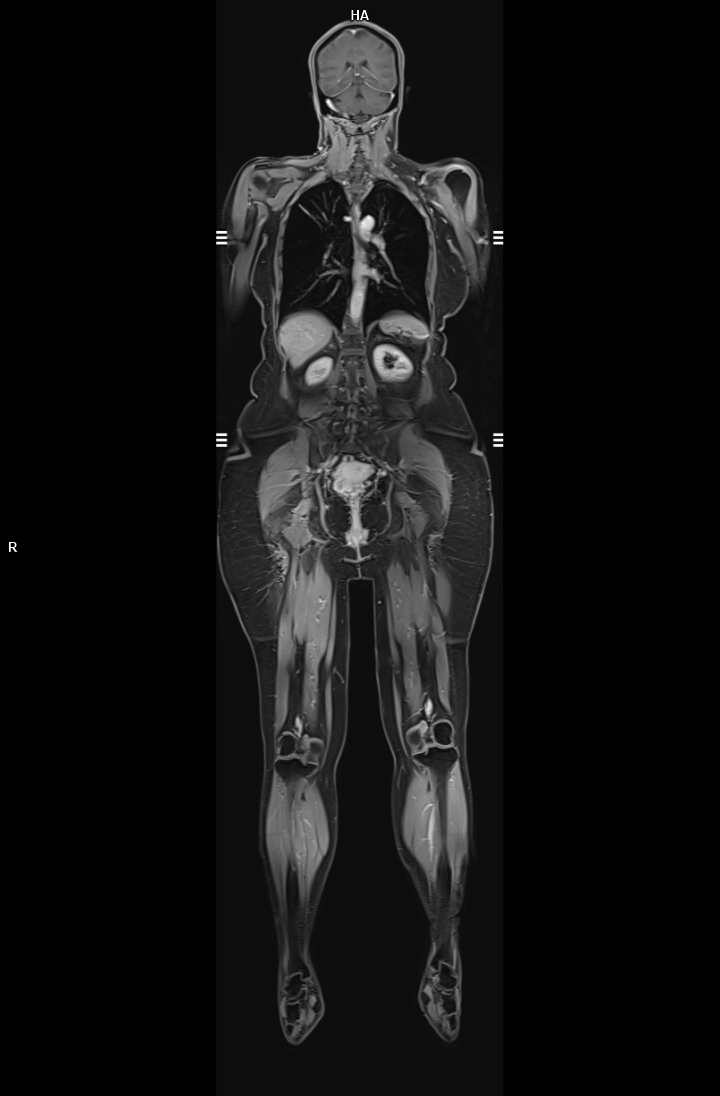

• 3 TESLA MR ÇEKİM GÖRÜNTÜLERİ

3 Tesla MR Çekim Görüntüleri

• 3 Tesla MR Çekim Görüntüleri